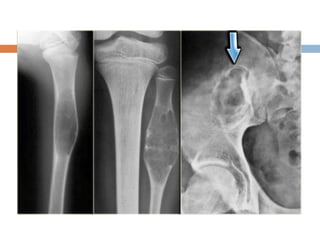

Xray

 Radiolucent area eccentrically at end of long

bone, bounded by sub-chondral plate

 Center has soap bubble appearance due to

ridging of surrounding bone

 Cortex is thin and ballooned

 Appearance of cystic lesion in mature bone

extending upto subchondral plate is

characterstic.

 Detail staging and extent of tumor can be done

by CT and MRI (imp to establish if articular

surface has been breached or not)